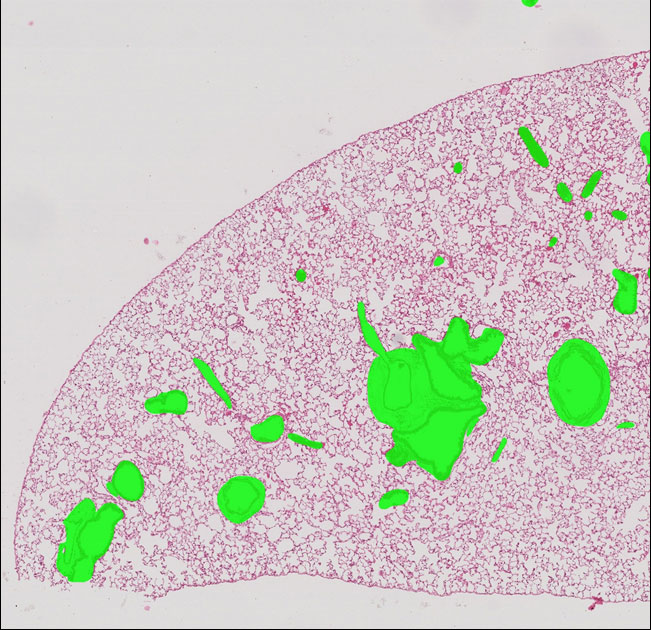

Lung Histology

After training and validating (3:1) on 16 whole slide scans, the neural network is able to identify a variety of areas in a normal mouse lung section (equivalent to 10X, cropped from whole slide scan).

The best results are listed below:

- single-class segmentation (dice)

- background: 97%

- conducting airway: 84%

- connective tissue: 83%

- large blood vessel: 78%

- respiratory airway: 97%

- small blood vessel: 63%

- multi-class segmentation (accuracy)

- all six categories: 96%

These methods are helpful for identifing and quantifing various structures or tissue types in the lung and extensible to developmental abnormality or diseased areas.

Non-Parenchymal Region Highlighted Image